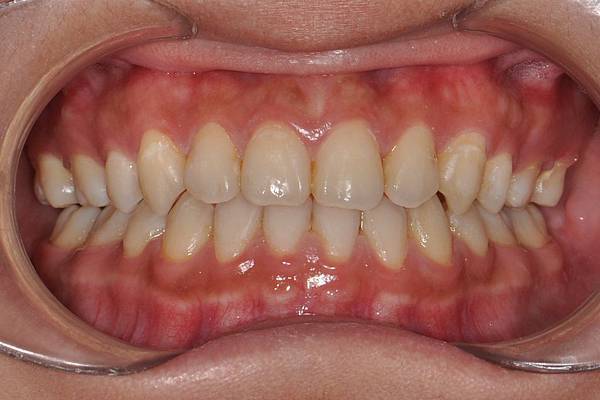

戽斗下唇突出改善案例

本案例因為考量到患者下唇突出

便建議拔除上下四顆小臼齒將

下唇內收

也改善了

前牙錯咬

的問題~

治療前/治療後

-以上案例由林昇進醫師提供